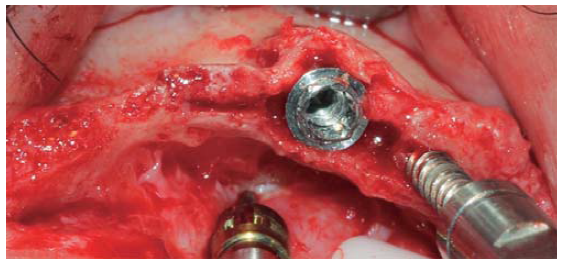

Se realizó una incisión supracrestal a espesor total, elevación del colgajo mucoperióstico exponiendo la tabla ósea hasta 4 mm de la cima de la cresta hacia vestibular y desde ese punto se dividió el colgajo a espesor parcial (Figura 3). Luego se marcaron los puntos de impacto en los sitios designados según la guía quirúrgica para la colocación de los implantes y se iniciaron las perforaciones con una fresa de 1.6 mm de diámetro para determinar el eje y profundidad deseada para los implantes. Luego se procedió a crear un surco a nivel crestal con un disco de diamante rompiendo el hueso cortical para crear el acceso a los escoplos al hueso esponjoso y con éstos se procede a separar las tablas óseas hasta llegar a una profundidad de 5 mm (Figuras 4 y 5). Seguidamente, se continuaron las perforaciones con una fresa de 2.0 mm de diámetro (Figura 6) y se realizó la expansión de la tabla vestibular creando una fractura en tallo verde con los expansores hasta alcanzar el diámetro del lecho óseo suficiente para poder utilizar la última fresa de 3.2 mm de diámetro (Figuras 7 y 8). Posteriormente, se colocaron los implantes a una velocidad de 25 rpm y a un torque de 35 Ncm (Figuras 9 y 10). Seguido de esto, se colocó un injerto óseo bovino particulado (Bonefill® Bionnovation Biomedical, Sao Paulo-Brazil), con la finalidad de preservar la integridad de las tablas óseas vestibulares (Figura 11). Todos estos procedimientos, se realizaron de la misma manera para la colocación de los seis implantes. Finalmente, se suturó con nylon monofilamento 5/0.

Figura 7 Ensanchamiento óseo utilizando expansores, creando un acceso adecuado para una fresa de mayor diámetro.

Figura 8 Expansor óseo ubicado distalmente en relación con la preparación previniendo una fractura de la tabla vestibular.